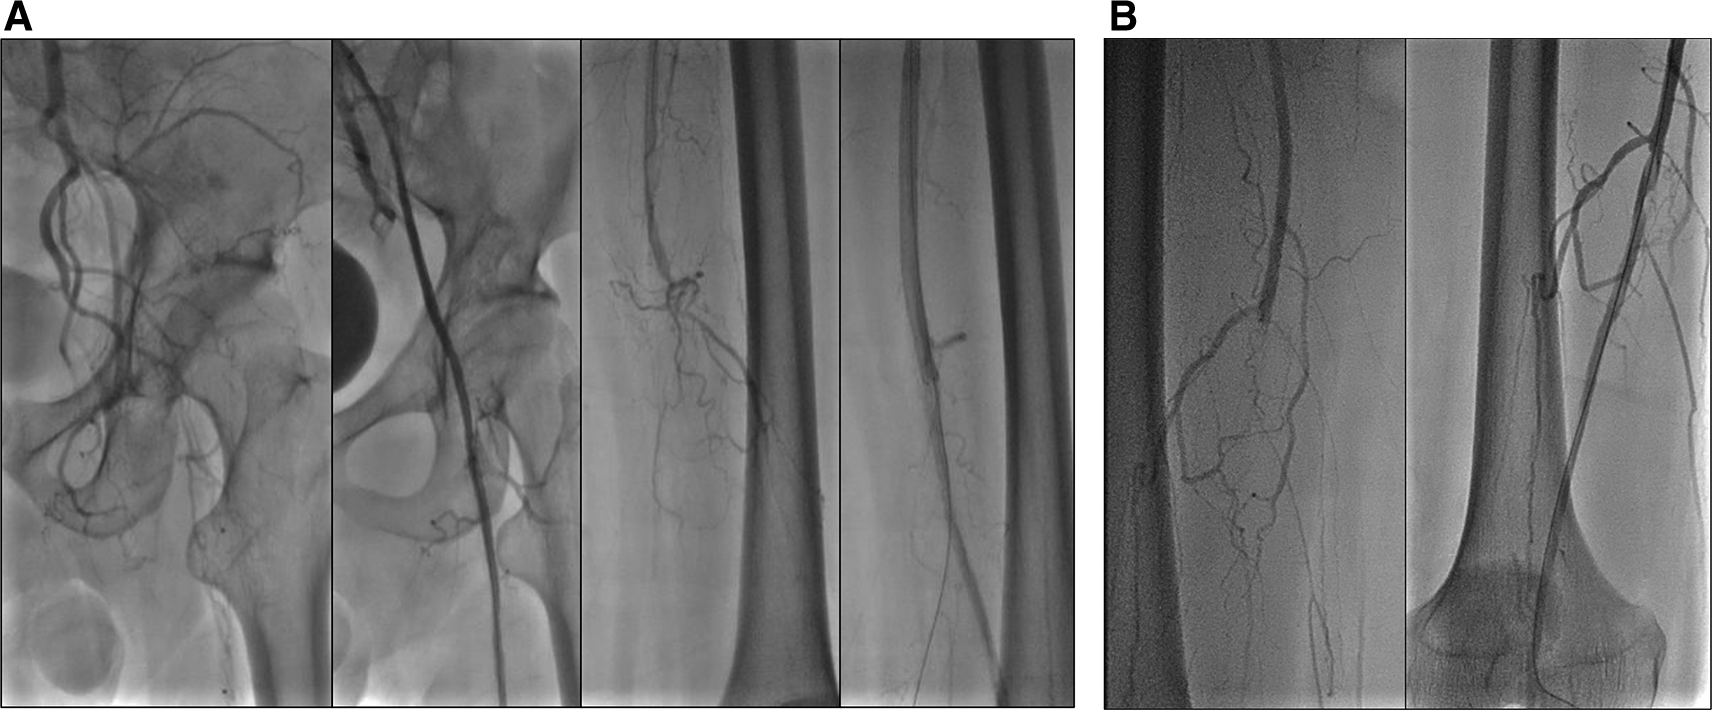

Vital signs were within normal limits. Physical examination revealed ulcer, hair loss, and atrophy on the left leg (Figure 5). Significant laboratory examination results were D-Dimer of 2990 ng/mL, total cholesterol of 233 g/dL, LDL of 187 g/dL, triglycerides of 164 g/dL, and urine albumin of 413 mg/L. His serum albumin was normal (184 g/dL). His right ABI was 0.5 on left was 0.33. Lower extremity DUS and CTA showed occlusion at level of left external iliac artery and 1/3 distal of right SFA with prominent plaque calcification (Figure 6A).

A. Pre-intervention, occlusion at level of left external iliac artery and 1/3 distal of right superficial femoral artery with prominent plaque calcification. B. Before 2nd intervention, positive flow until distal of the left leg with patent stent.

The patient’s diagnosis at the time was CLTI with ulcer on the left leg (Rutherford III-5, WIFi Score 1-3-0), chronic limb ischemia on the right leg (Rutherford I-3, WIFi Score 0-2-0), TASC II type D lession, and nephrotic syndrome. He was treated with heparinization and two episodes of percutaneous transluminal angioplasty (PTA). First, with POBA done at left Iliac Artery and SFA with addition of 6.0 × 120 mm drug-eluting stent (DES) overlapped with 6.0 × 80 mm (Boston Scientific, Marlborough, MA, USA) at SFA (Figure 7A). Second, POBA at mid–distal right SFA 5 months later (Figure 7B). CTA after the first procedure (Figure 6B) and angiography after second procedure with lower extremity DUS confirmed positive flow until distal vessel of both lower limbs. The patient was discharged without any complaint and received rivaroxaban, clopidogrel, aspirin, simvastatin, mycophenolic acid, and methylprednisolone as his routine medication. he was also educated to do exercise therapy.

A. First intervention, contrast flow until distal of left leg artery after percutaneous transluminal angioplasty. B. Second intervention, contrast flow until distal of right leg artery after percutaneous transluminal angioplasty.